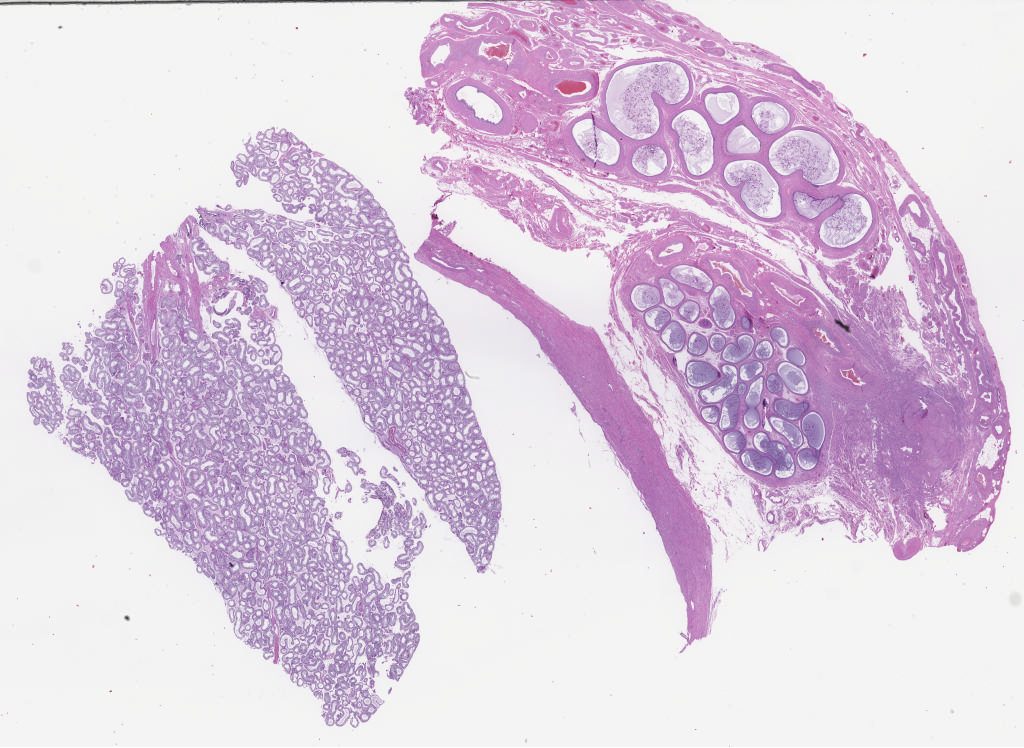

277779.svs

40X